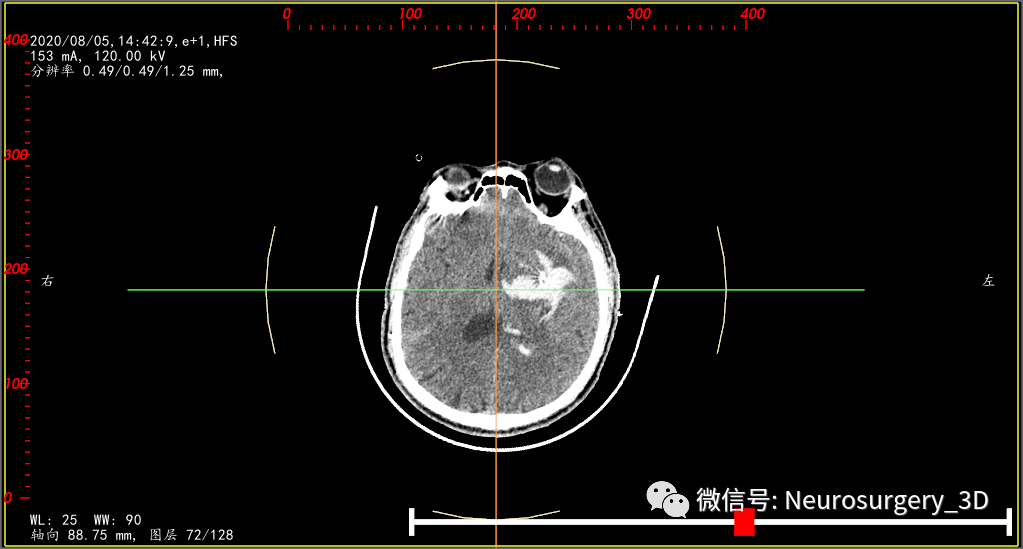

再来一例病例(2020年8月5日9:39)入院,王友某,男,61岁,入院时CT,也是高低密度分层,像不像活动性出血?

微创钻孔置管引流术后4小时CT复查(引流管位于血肿中心)

由以上两例病例可以看出,第一例选择微创治疗方案是因为,其一:多次CT复查,高密度血肿增加不明显,所以第一例选择微创穿刺置管是比较恰当的(个人认为

);其二:低密度血肿半包围于高密度血肿周围;其三:病情发展缓慢,时间允许三维设计、打印导板。第二例选择微创穿刺置管并不是最终的目的,而是为了争取术前准备时间,先行床边引流,迅速减压,为进一步开颅创造机会。但是根据复查CT,血肿没有增加可,故而选择继续保持引流,如果引流后出血不见减少或增加可随时选择手术(术前准备已完善);第二例至于为什么不考虑微创为首选,因为其完全不具有第二例血肿的特征,万幸其微创也达到了目的,但是其不具有特征性,不具有参考价值。